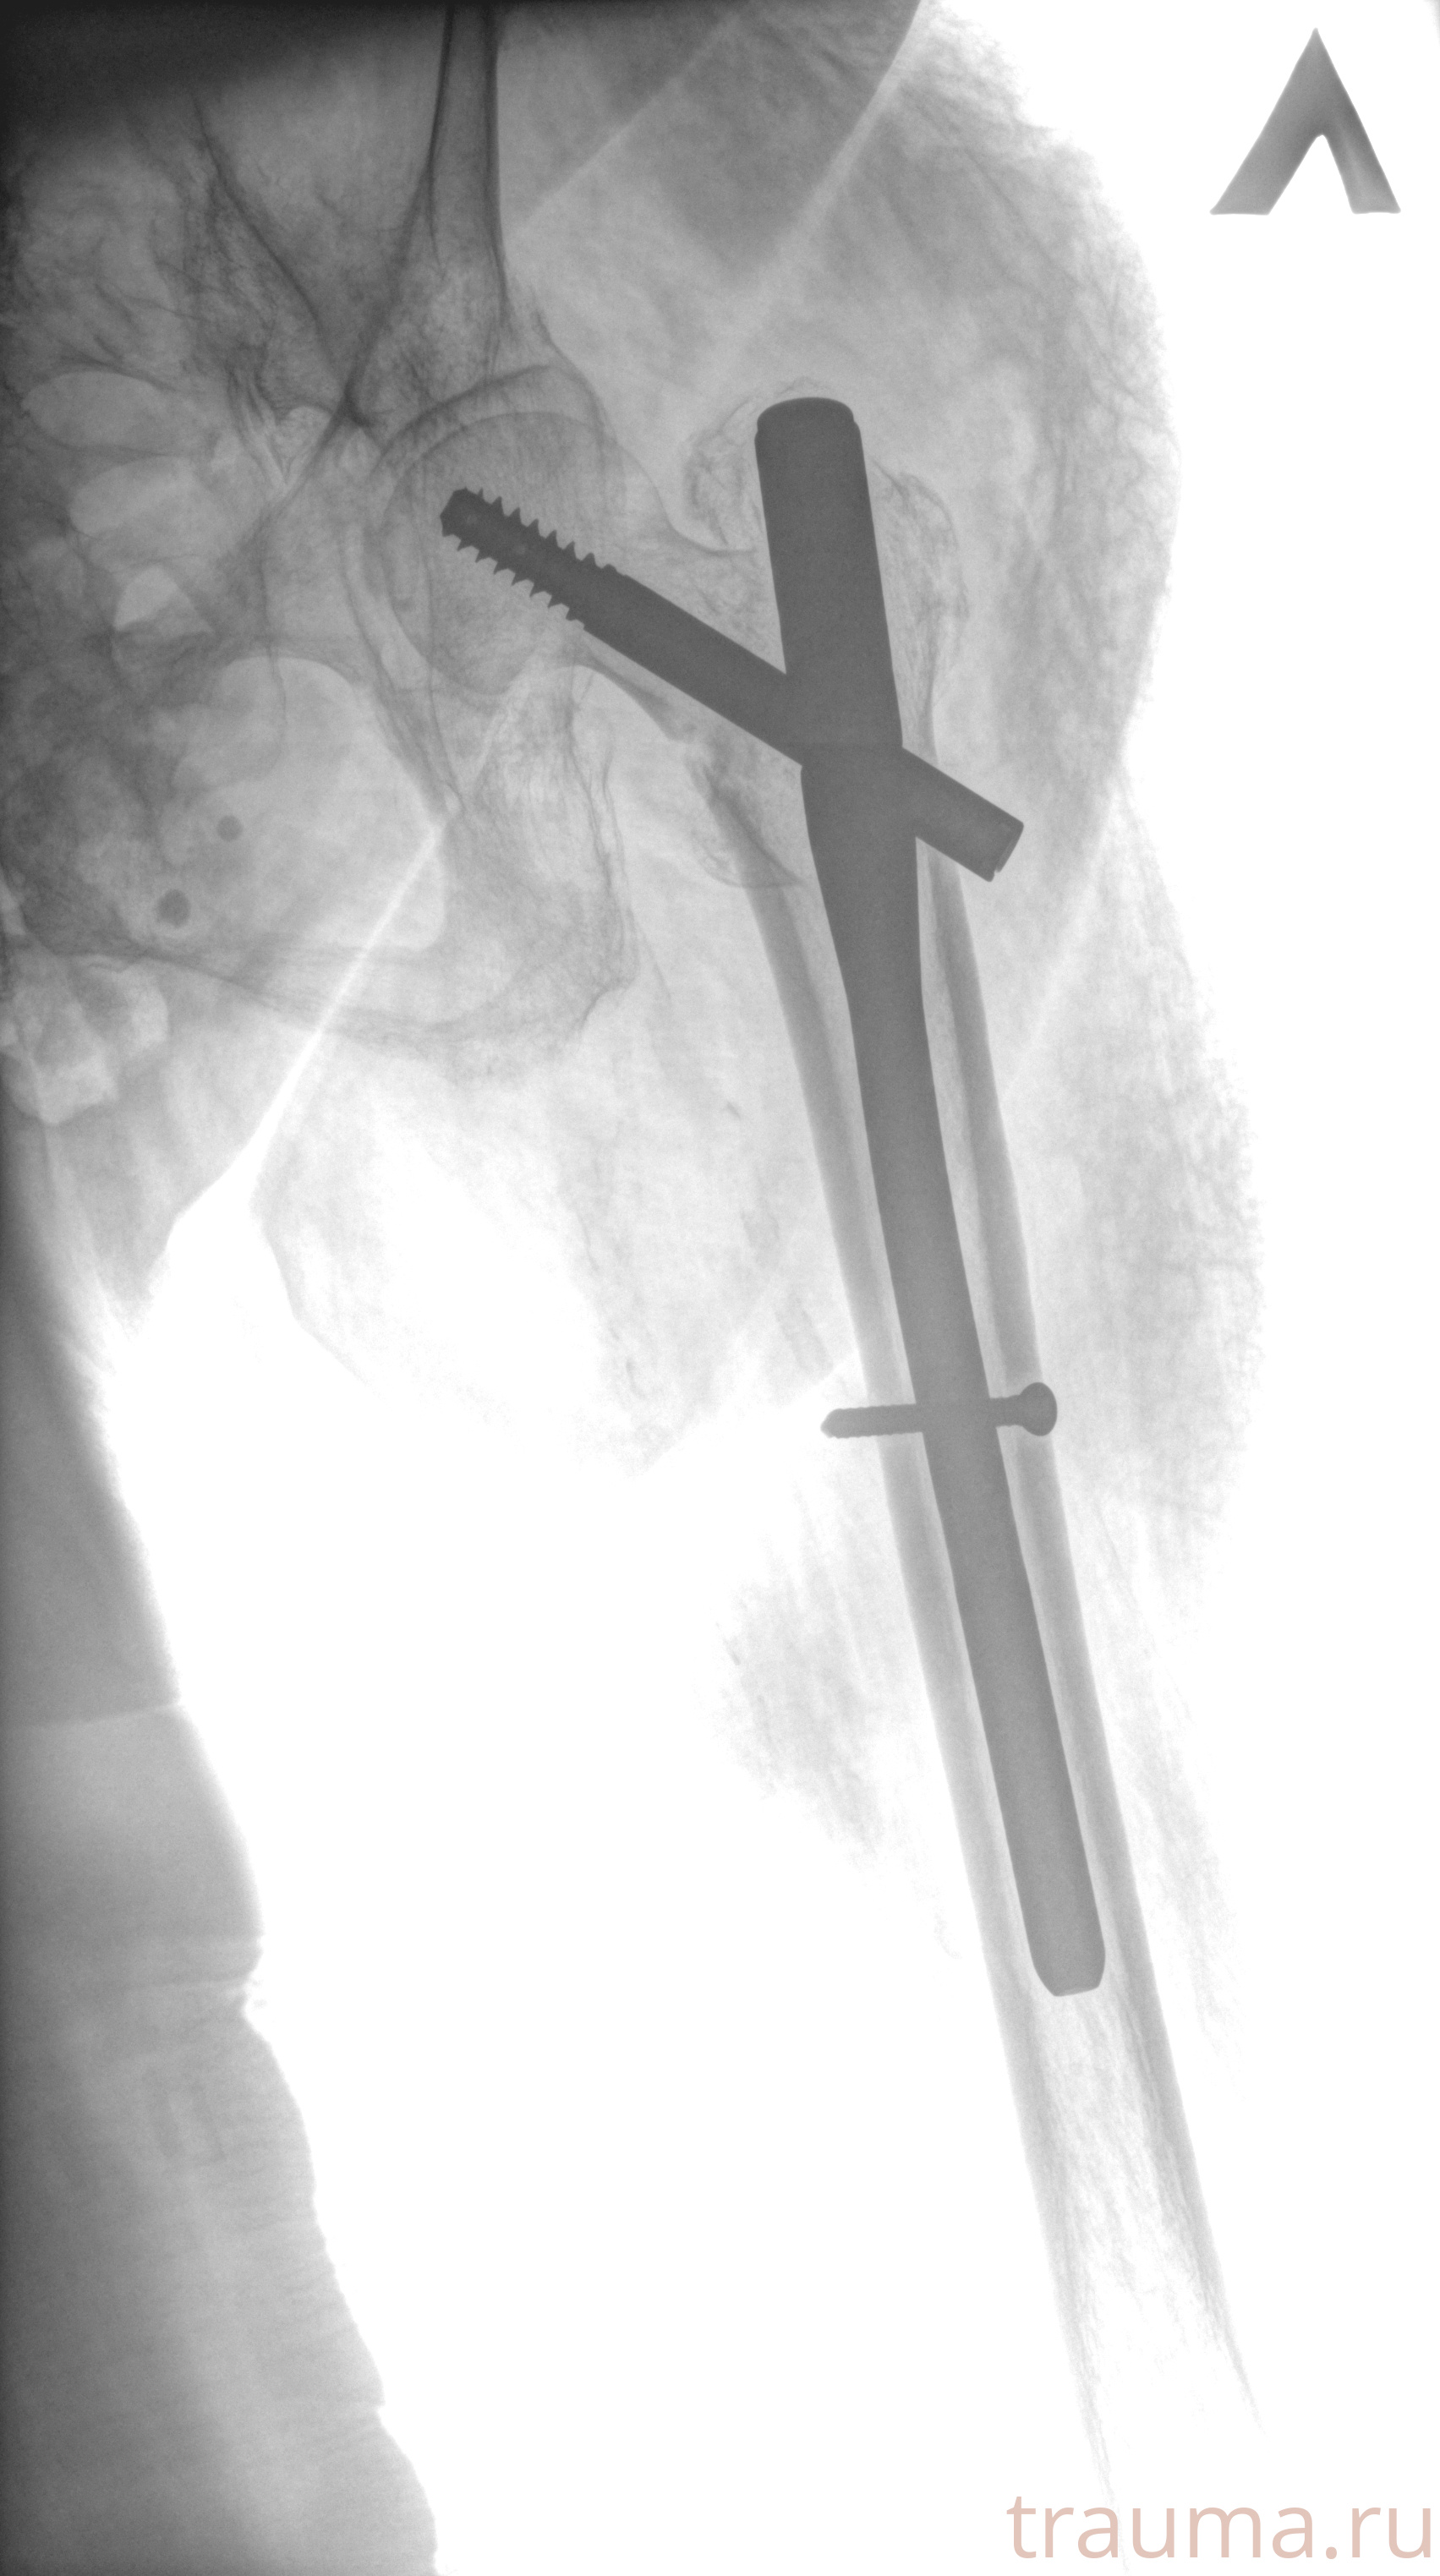

Рентгенограммы